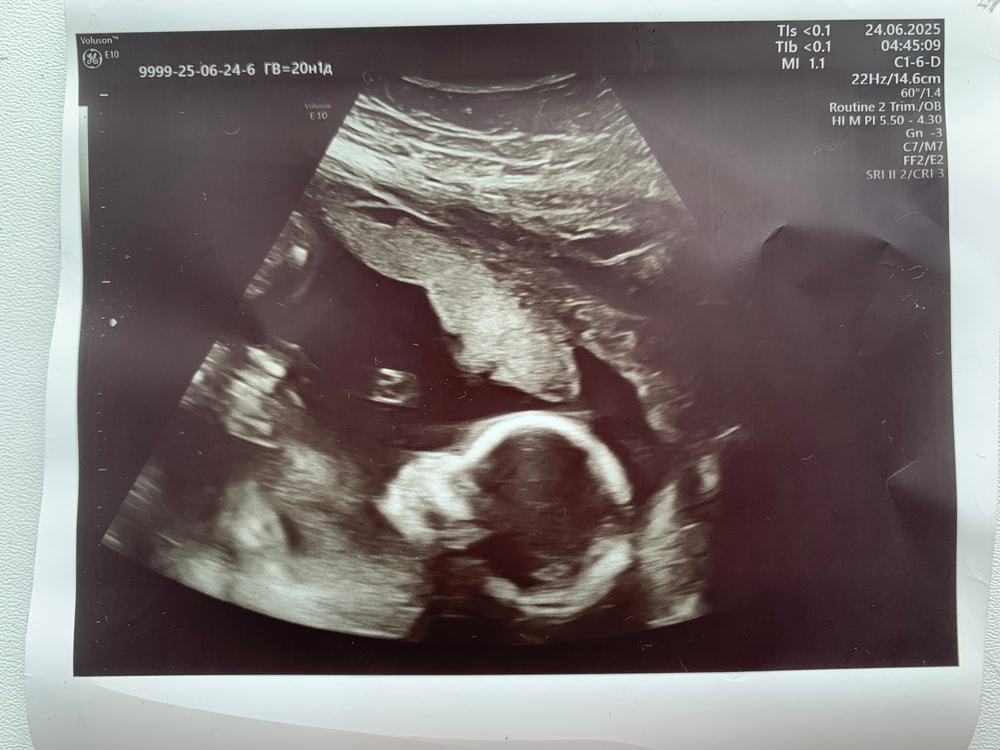

20 недель. 2 скрининг 🎊

Результаты: УЗИ, КТГ, доплера, скрининга

Всем привет. Вчера был 2 скрининг. Все хорошо, малышка весит 300 грамм. Рубец 4 мм, шм 40 мм. Очень активная, испинала весь датчик 🤪